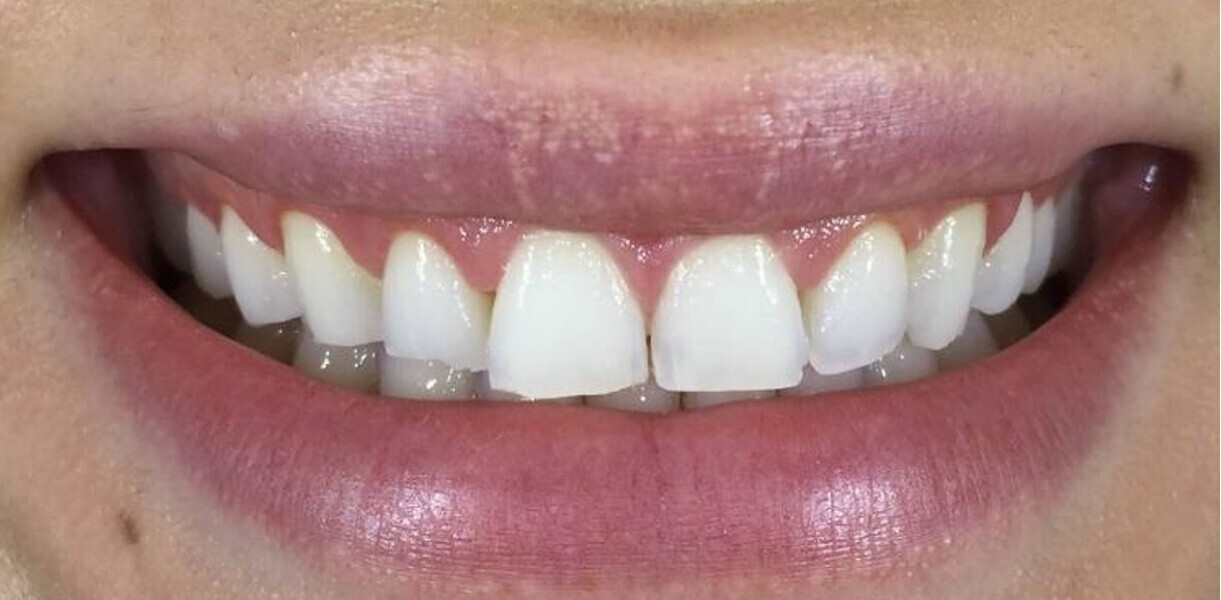

After six months of weekly changeover of aligners (25 out of 33 aligners in the maxillary arch and 25 out of 25 aligners in the mandibular arch and no refinement) and achieving adequate intrusion of the six maxillary anterior teeth, the pre-restorative segment of the treatment was complete (Figs. 5 & 6). The next phase was a digitally planned soft-tissue recontouring of the labial tissue of the six maxillary anterior teeth. For this purpose, a digital surgical guide was made by our laboratory at AORTA using our PRO 4K printer (Asiga; Figs. 7–10). This was followed by in-chair tooth whitening and then composite augmentation of the incisal edges of teeth #13–23 (Figs. 11 & 12). The patient was then placed into retention with Zendura FLX thermoplastic retainers (Bay Materials) based on resin 3D-printed models produced by our PRO 4K printer, providing accuracy and superior fit as observed by the patient. The retainers and models were all made by our dental laboratory at AORTA.

Fig. 6: Close-up view of the patient’s smile after aligner treatment.

Fig. 12: Close-up view after soft-tissue recontouring, direct restoration and whitening.